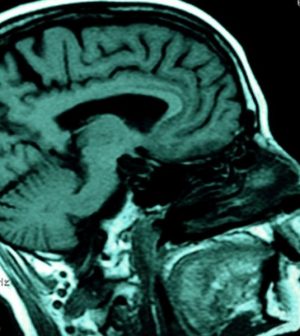

Through their tests with these patients, the researchers were able to identify an area in the left brain that appears specialized to process spoken words.

“The fact that only the auditory words were impaired in these patients and their visual words were untouched leads us to believe we’ve identified a new area of the brain where raw sound information is transformed into auditory word images,” Weintraub explained in a university news release.